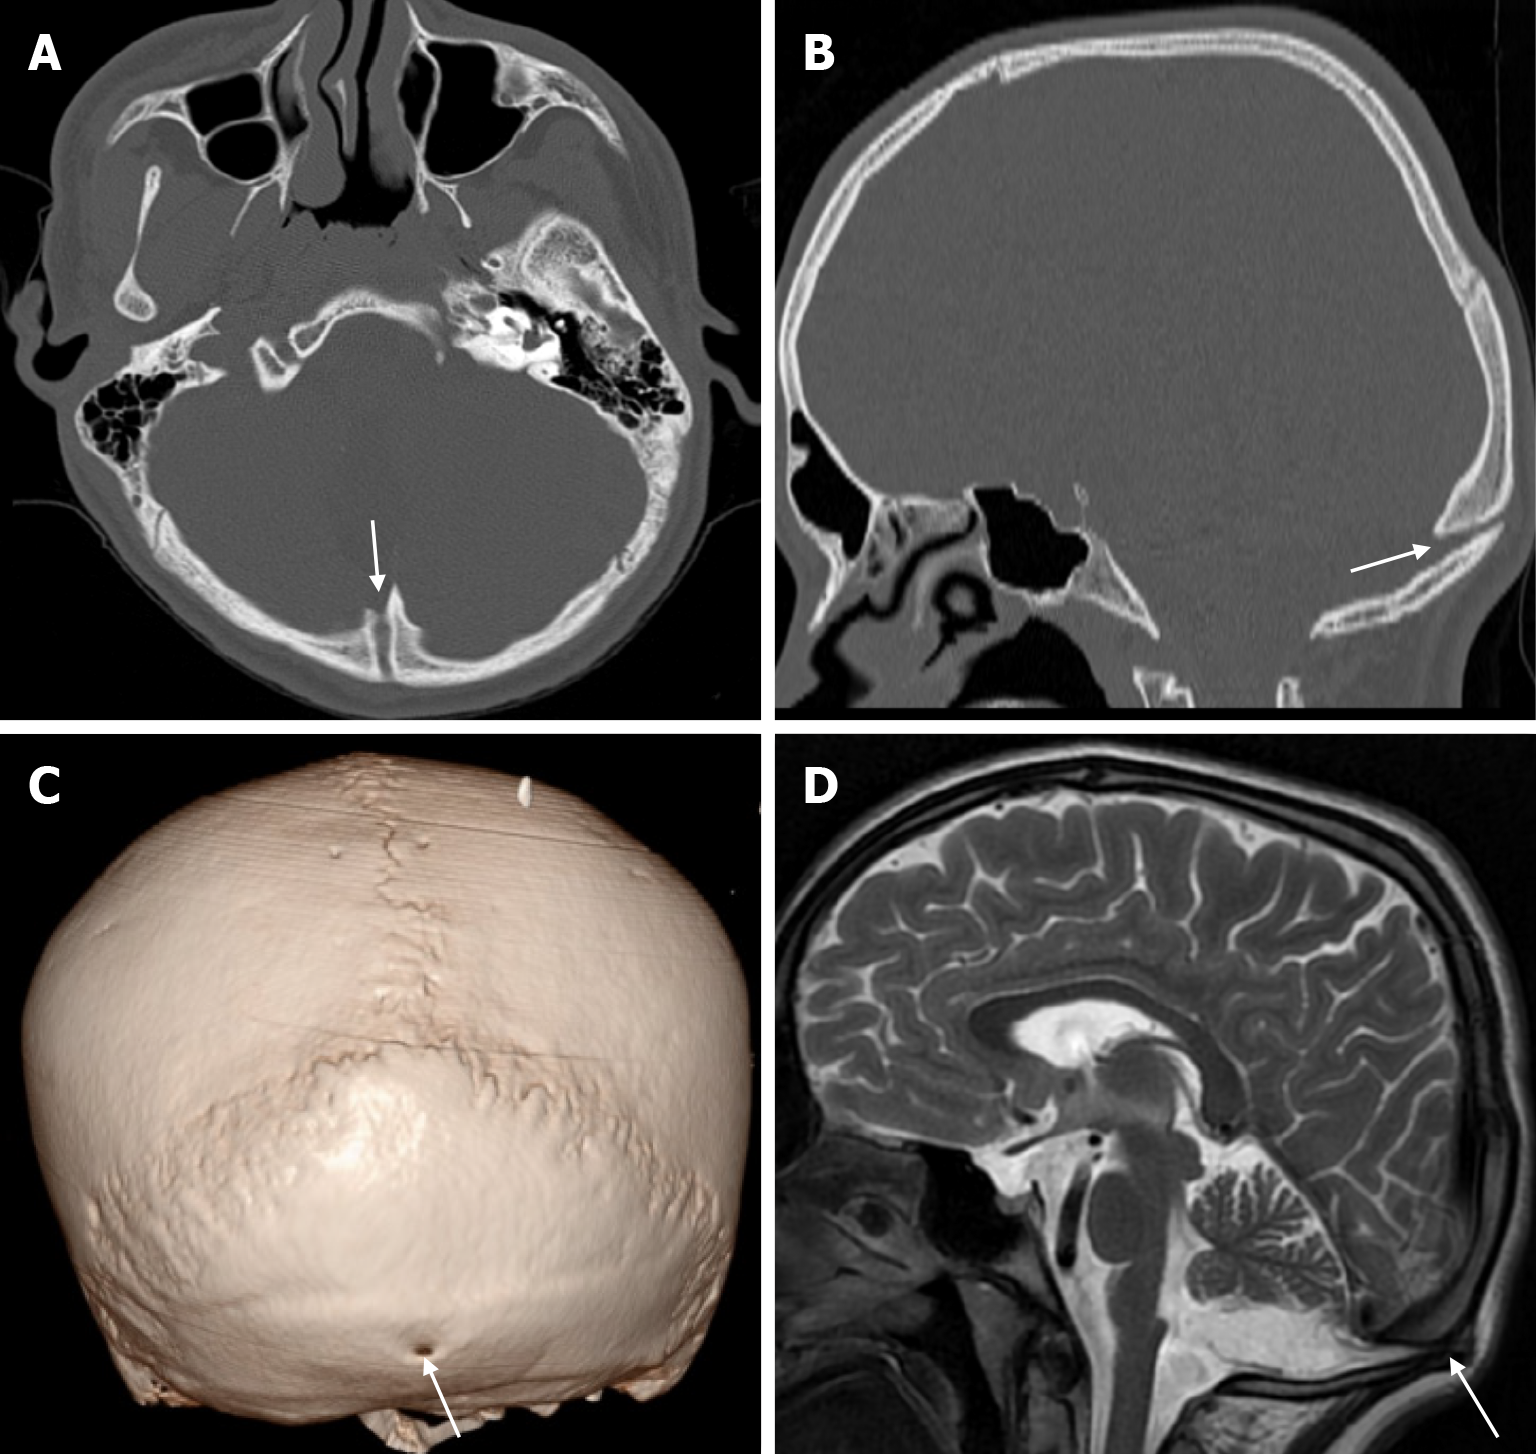

Atretic encephalocele is a midline scalp mass covered by skin containing meninges and neural remnants and/or degenerated brain tissue. In atretic encephaloceles, the brain tissue in the scalp degenerates and may remain attached to the dura mater by a fibrous stalk intracranially. Atretic cephaloceles may be associated with a persistent falcine vein characterized by a vertical embryonic position of the straight sinüs (Figure 6). Most atretic encephaloceles are parietal in location. On CT imaging, a subgaleal soft tissue mass may be seen in a “spinning top” configuration. CT imaging helps visualize bone defects, while MRI helps determine the contents of the encephalocele[3]. The lesions most commonly confused with atretic encephaloceles are sinus pericranii and dermoid cysts[25].